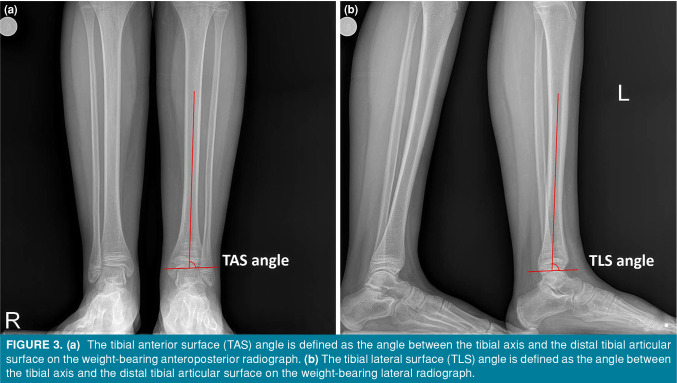

Patients and methods: Between January 2015 and January 2021, a total of 46 patients (37 males, 9 females; mean age: 11.9±2.5 years; range, 6 to 16 years) who were operated within 12 h due to displacement >2 mm after reduction were retrospectively analyzed. Demographics, fracture type (Salter-Harris [SH]), fracture mechanism (Dias & Tachdjian [DT]), accompanying fibula fracture, and initial displacement were assessed with preoperative radiographs. At two years of follow-up, PPC, angular deformity, and length discrepancy were evaluated.

Abstract Image